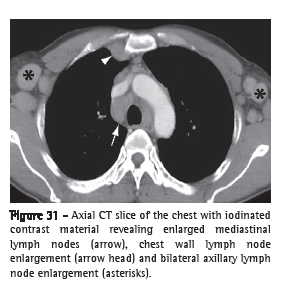

Lymph node enlargement (linfonodomegalia)

Lymph node enlargement is characterized by the increase in volume in one or more lymph nodes, due to any cause, surpassing the dimensional limits considered normal for the lymph node chain in question (Figure 31).(52,53) The term "adenomegaly" is not an acceptable synonym, since lymph nodes are not true glandular structures. The term "linfonodopatia" ("lymphatic disease") is reserved for situations in which a disease, such as necrosis, has been identified within a lymph node.